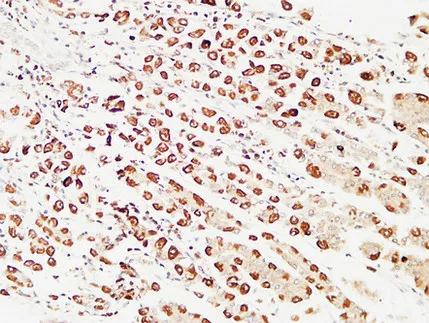

HSP90β (phospho Ser254) Rabbit Polyclonal Antibody

Cat: APRab04808